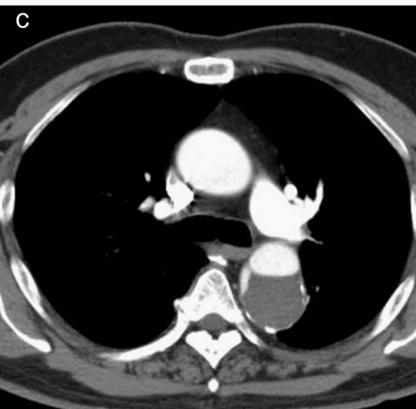

增强CT一看,主动脉夹层,密度相对高的是流动的血液!

增强CT一看,主动脉裂开了!